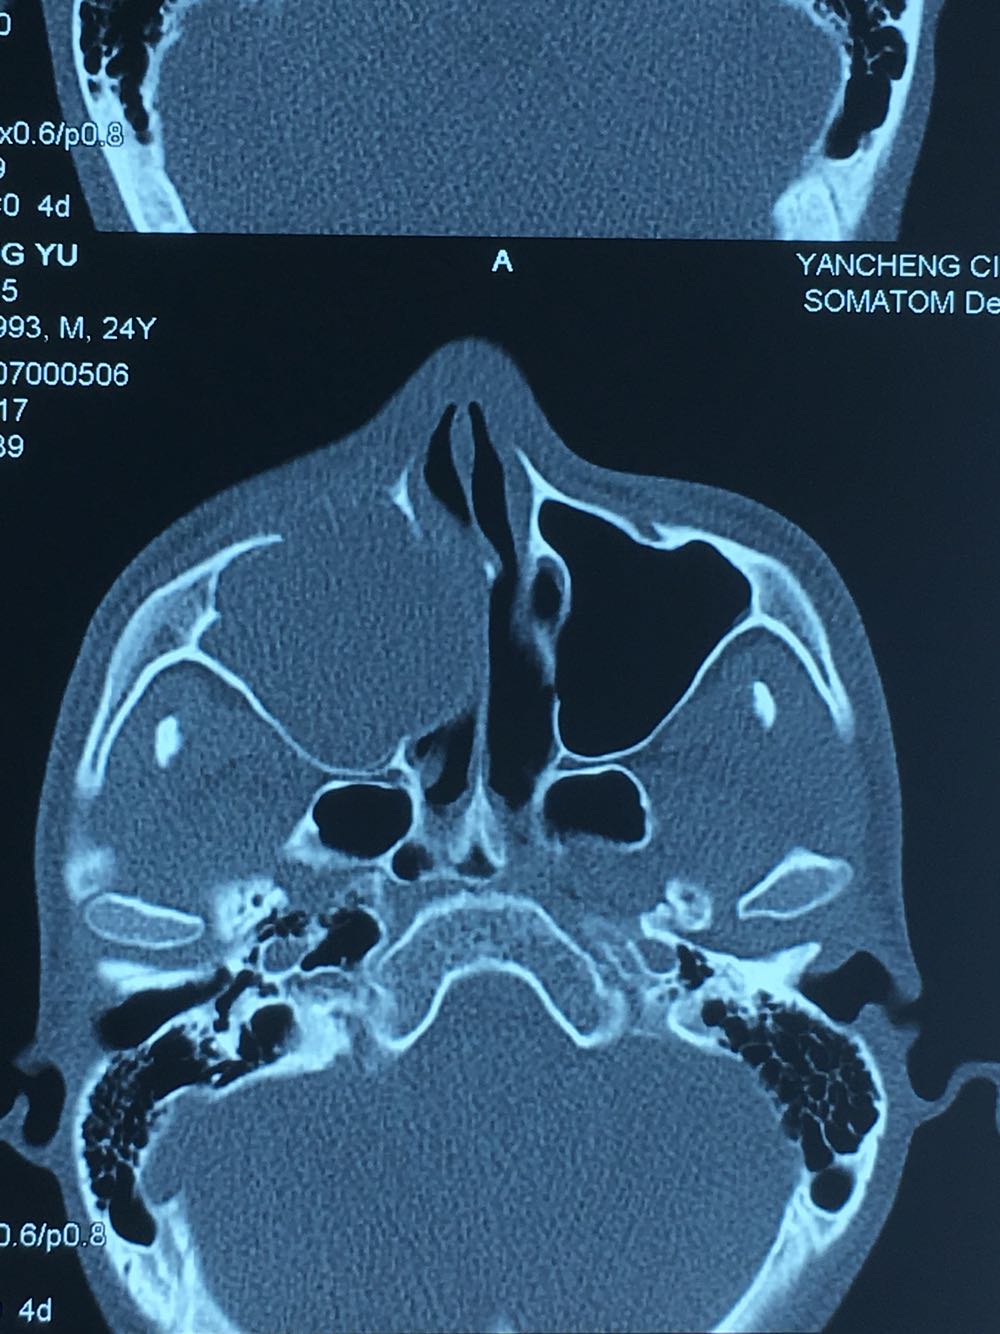

查体:面部明显不对称,右上颌膨隆明显,右鼻翼抬高,眶下区无麻木感,眼球运动自如,13牙齿缺如,16-22牙齿唇侧前庭肿胀,中央扪及波动感,边缘乒乓感,相关牙齿1度松动。 辅查:穿刺,抽得淡黄色液体,全景及CT,上颌骨囊肿,右侧上颌骨骨质大部分破坏

诊断:右上颌骨囊肿,13埋伏阻生。 治疗:开窗减压,拔除13阻生牙齿